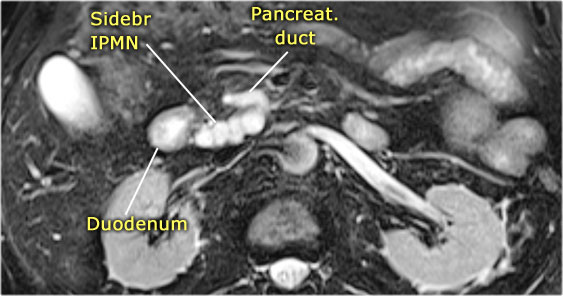

MRI shows a lesion, which consists of multiple small cysts.

This could be a serous cystic neoplasm or a branch-duct IPMN.

The connection of the cystic lesion to the pancreatic duct indicates that this is a branch-duct IPMN.